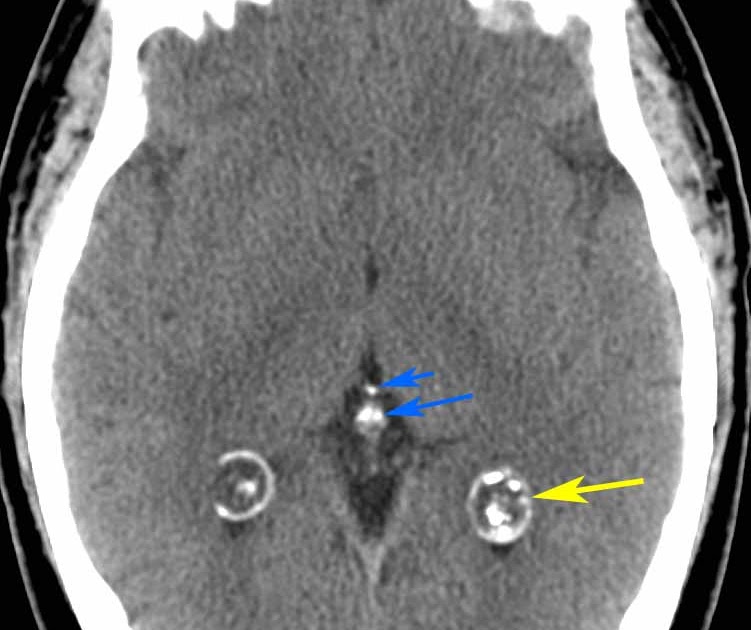

There were 44 males and 16 females. Computed tomography (ct) scanning may be needed to evaluate a calcified pineal gland that is associated with a pineal germinoma or tumor calcification associated with other neoplasms in the pineal. Axial view of a head computed tomography (ct) scan of pineal gland calcification in the very center of the brain fluoride is the.